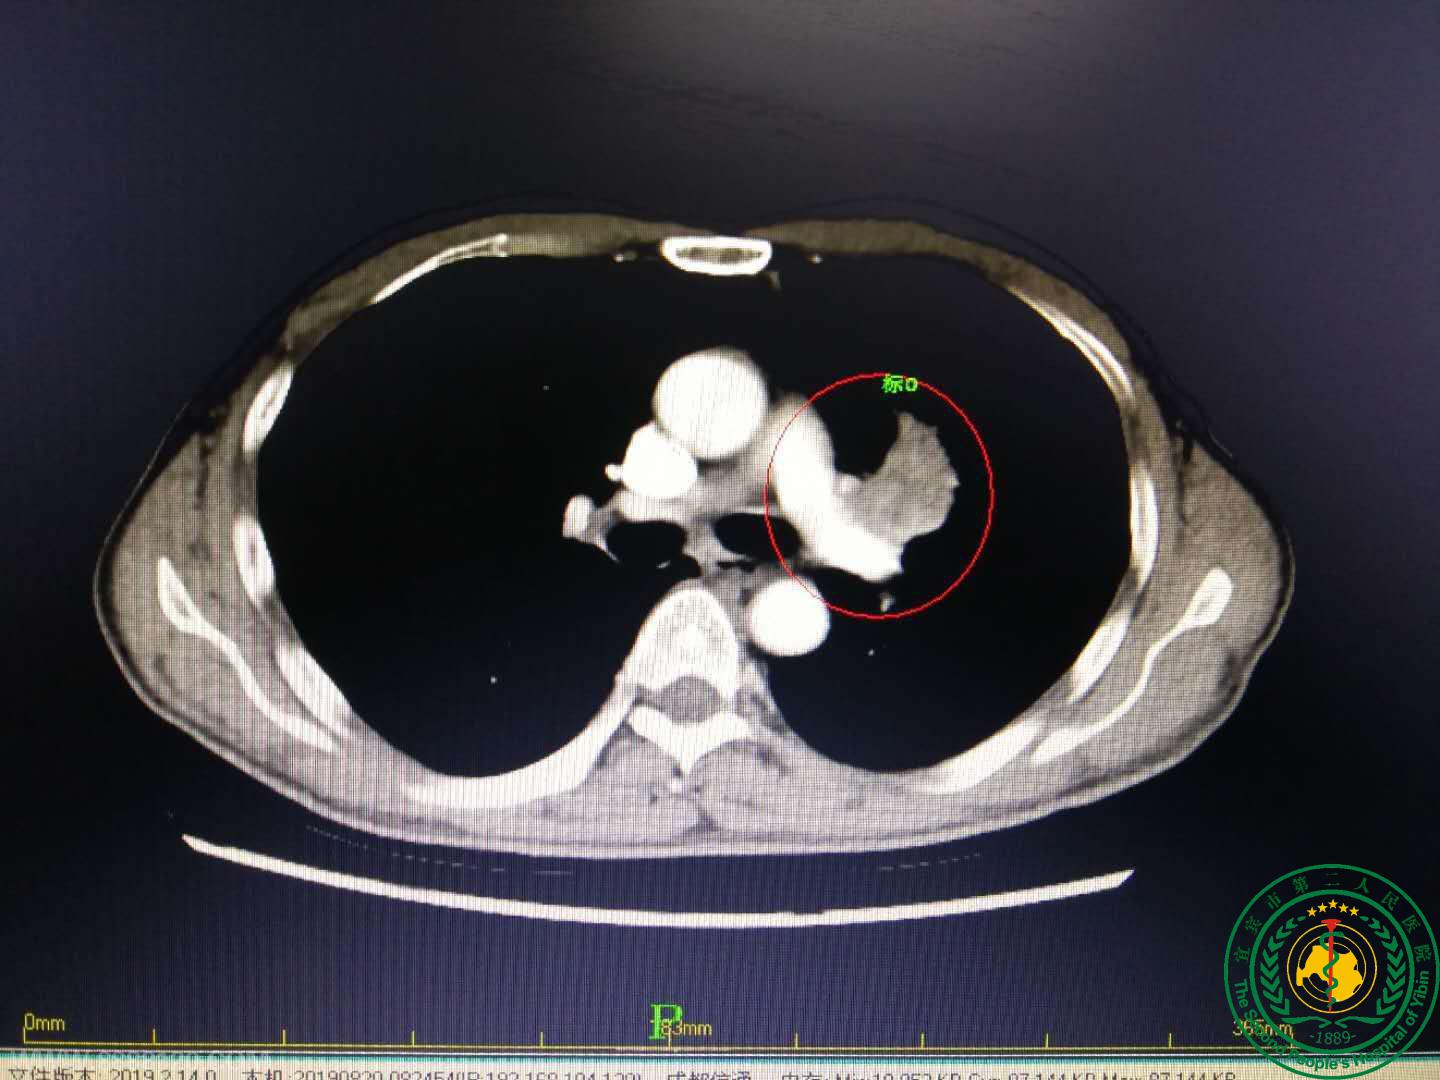

宜宾二医院率先在川中南独立成功开展胸腔镜辅助肺动脉支气管双袖式肺叶切除切除

宜宾二医院率先在川中南独立成功开展胸腔镜辅助肺动脉支气管双袖式肺叶切除切除26868